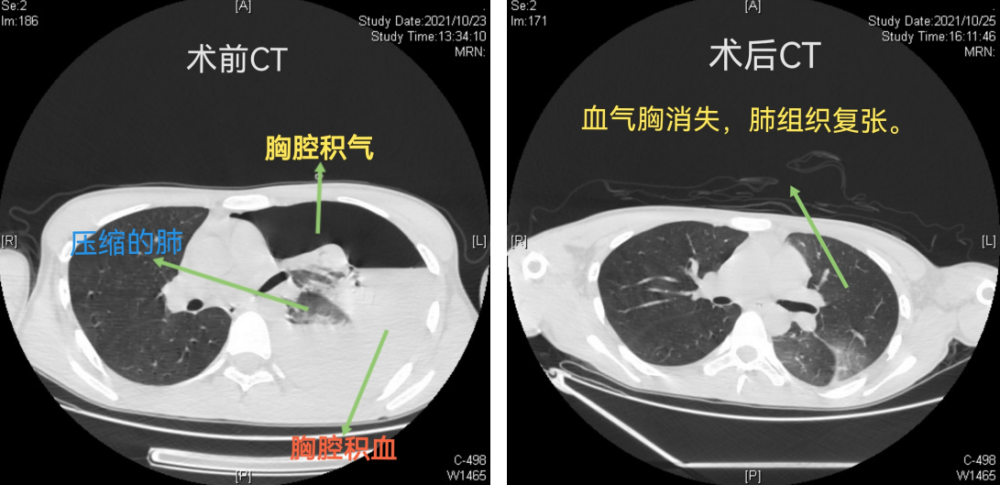

长沙市中心医院(南华大学附属长沙中心医院)胸外科、心脏大血管外科主任、主任医师袁跃西介绍,当天患者由120救护车送到急诊科后,主治医师苏英杰迅速为患者完善胸部CT检查,结果发现其左侧大量液气胸,高度怀疑血气胸。

手术中,主刀医生杨继承发现患者左侧胸腔出血约有2000多毫升,胸顶有一撕裂小动脉出血,左上肺有多个肺大疱。

立即用自体血回输装置进行胸腔出血回收,随后将出血小动脉用超声刀凝固止血,并将肺大疱切除,手术顺利完成,患者转危为安。